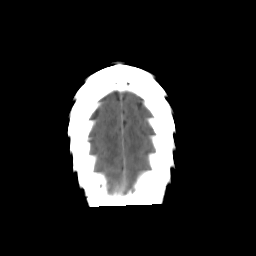

Stroke CT #3 -- Slice #22

[Home][Help][Clinical] Slice 22